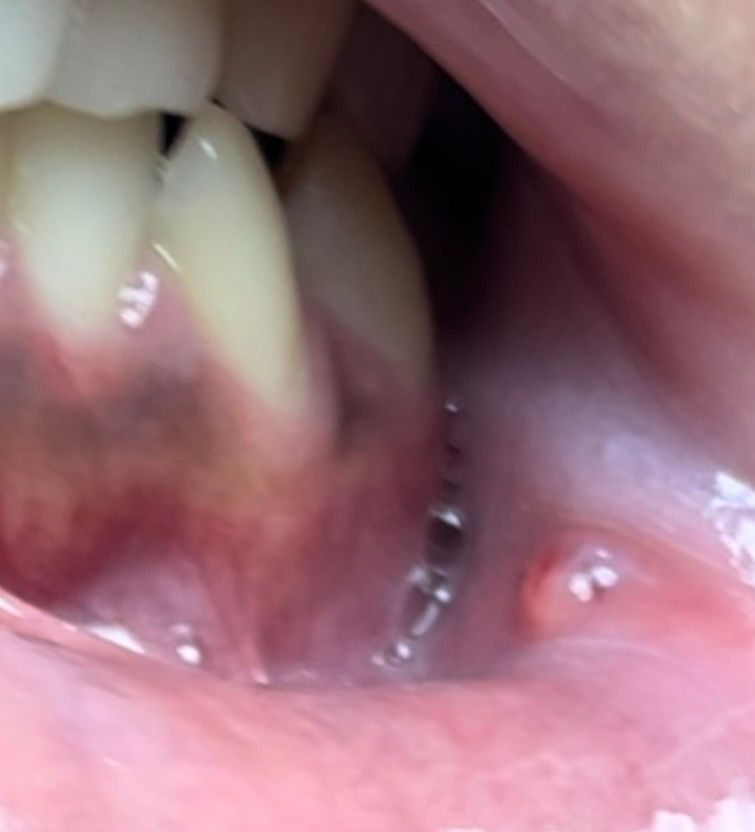

구강암인가요 6~10일 사이 정도 된 거 같아요 6년 흡연자고 20대 초반입니다

처음엔 완전 구내염이었는게 갑자기 생김새가 조금 변한 거 같아 무섭네요 알려주시면 감사하겠습니다

막 살펴보다가 봤는데 이 동그란 건 또 뭔지 알 수 있을까요

단순 구내염 혹은 물집 정도로 보입니다. 며칠 이내에 사라질 것 같으니 너무 걱정하지 마세요

구강암은 아니니 너무 걱정하지마세요. 잇몸에 물집이 생긴거 같으니 터트리시면될것같습니다.

단순한 구내염일수도 있으니 자세한 확인을 위해서 치과에서 진료를 받아보세요.

사진상으로 구강암으로 보이지는 않으며, 구내염으로 보입니다. 시간이 지나면 좋아지게 되나, 소독용 헥사메딘 가글액으로 가글하여 관리하는 것이 도움이 되며, 구내염 연고를 바르는 것도 도움이 됩니다.